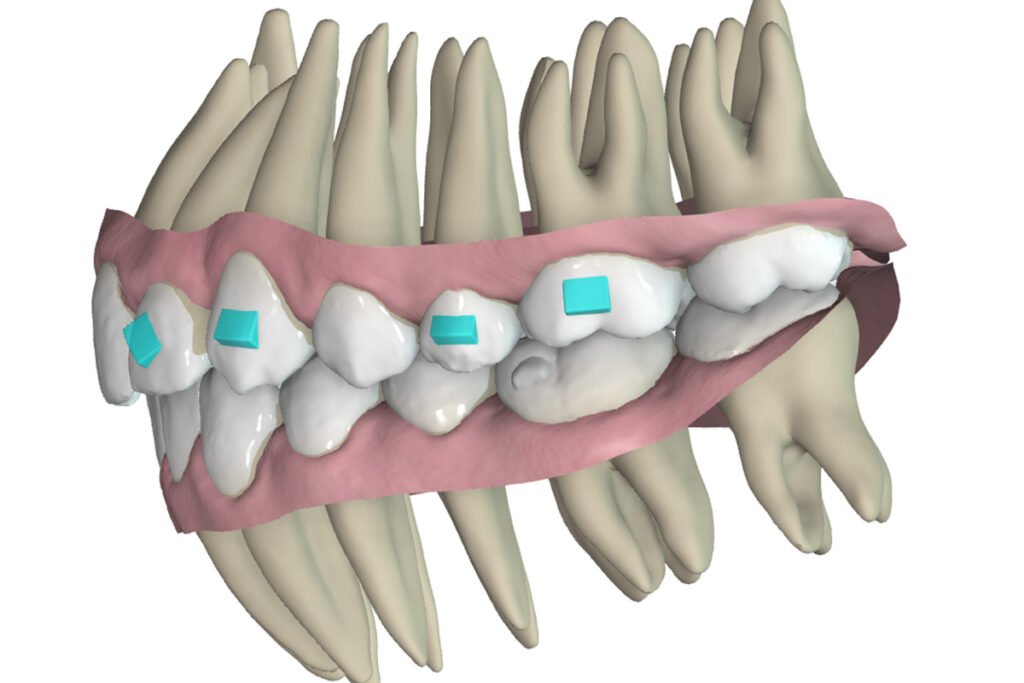

This article describes the treatment with Spark Clear Aligners of a 13 years-old female patient, who presented a CLASS II DIV. 1 caused by mandible retrusion, hypodivergent profile, crowding and constriction in both arches, high positioned canines, 6mm of deep bite and strong curve of spee.

Description of treatment plan

Having in mind the CS2 growth pattern presented by this patient, the treatment goal established was to correct the Class II by performing mandibular advancement – class II mechanics with elastics- together with upper arch retraction, while the deep bite was corrected through lower incisor intrusion and premolar extrusion. Also, expansion was planned to correct the arch constriction and create spaces to correct the crowding.

To perform this, the following was planned in the Approver: expansion of both arches, applying buccal root torque in molars and premolars, derotation of 6s and flatten the curve of spee. In order to flatten the curve of spee, intrusion of incisors and second molars, together with premolar extrusion were requested. Also, identifying the need to have enough overjet for the planned movements, we had to overcorrect proclination of upper incisors and relative intrusion. Having identified that there was gum transparency in the root surface of lower incisors, also lingual root torque was requested for these teeth. Also, the auxiliaries used to apply class II biomechanics were buttons in both canines and molars.